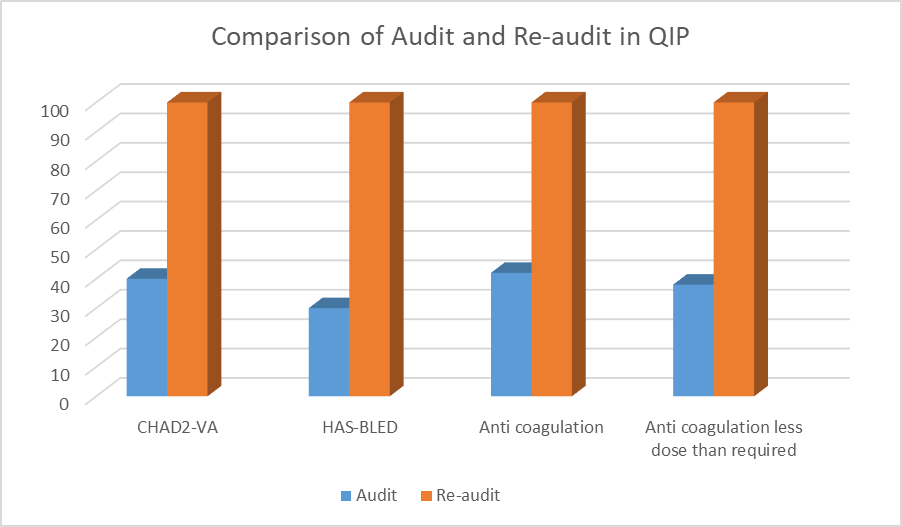

Quality Improvement Report | Oct 14, 2024

A Quality Improvement Project Focused on Clinical Audit and Re-Audit on the Use of Anticoagulation in Atrial Fibrillation Patients with International Guidelines

This Quality Improvement Project (QIP) aimed to enhance the management of anticoagulation therapy in atrial fibrillation (AF) patients by improving...Read More